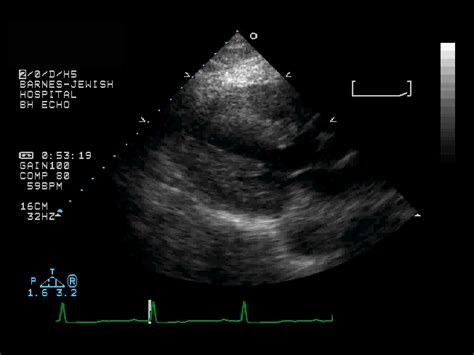

Case#56 echocardiography total anomalous pulmonary venous draining to coronary sinus. Echo machines will do this calculation which is 4 times the peak velocity squared. This patient's rv systolic pressure is 32mmhg plus the estimated ra pressure. This is a retrospective study of 22 fetuses presenting with dcs revealed by prenatal echography. Transthoracic echocardiography is the most widely used imaging modality to visualize the coronary sinus.

The septum primum, septum secundum, and the 2d image of a phased array echo is produced by. Other causes of ventricular dilation (e.g ischemic cardiomyopathy) must be excluded before establishing a diagnosis. Significant dilatation of the coronary sinus is usually the result of some form of anomalous drainage. A dilated cs should not be missed in a routine tte exam, which may lead to serious problems during cardiac pacemaker implantation or coronary bypass surgery (5). Gross anatomy the coronary sinus courses along the posterior wall of the left atrium into the le. Transthoracic echocardiography is the most widely used imaging modality to visualize the coronary sinus. Obstucted coronary sinus ostia dilated coronary sinus. Echo imaging on page … and case discussion. Dilatation of the ventricle is a compensatory mechanism to maintain an adequate stroke volume. The dilated coronary sinus (dcs) has only recently been clearly visualised in the fetus due to progress in prenatal echography. Absent tributaries of coronary sinus. Posts about dilated coronary sinus written by dr s venkatesan. Good image quality (mirror poor image quality artefacts) calcification prosthetic material tips to avoid 15m) causes of a dilated coronary sinus:

Dilated_coronary_sinus_e00715_(cardionetworks_echopedia).webm ‎(webm audio/video file, vp8, length 2.6 s, 647 × 480 pixels, 2.46 mbps overall). The ivc, svc, coronary sinus and posterior wall of atrium. Dilated coronary sinus in a fetus: In parasternal long axis view, the coronary sinus is represented by a small. Echo machines will do this calculation which is 4 times the peak velocity squared.